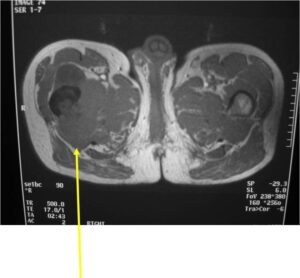

Radiology emulates pathology: Biphasic Tumor

- One region low grade chondrosarcoma

- Second more aggressive area with bone destruction, lysis of calcification, soft tissue mass

- Cortical permeation and a soft tissue mass in 70% of cases

Characteristically abrupt transition between chondroid tumor and dedifferentiated, lytic component